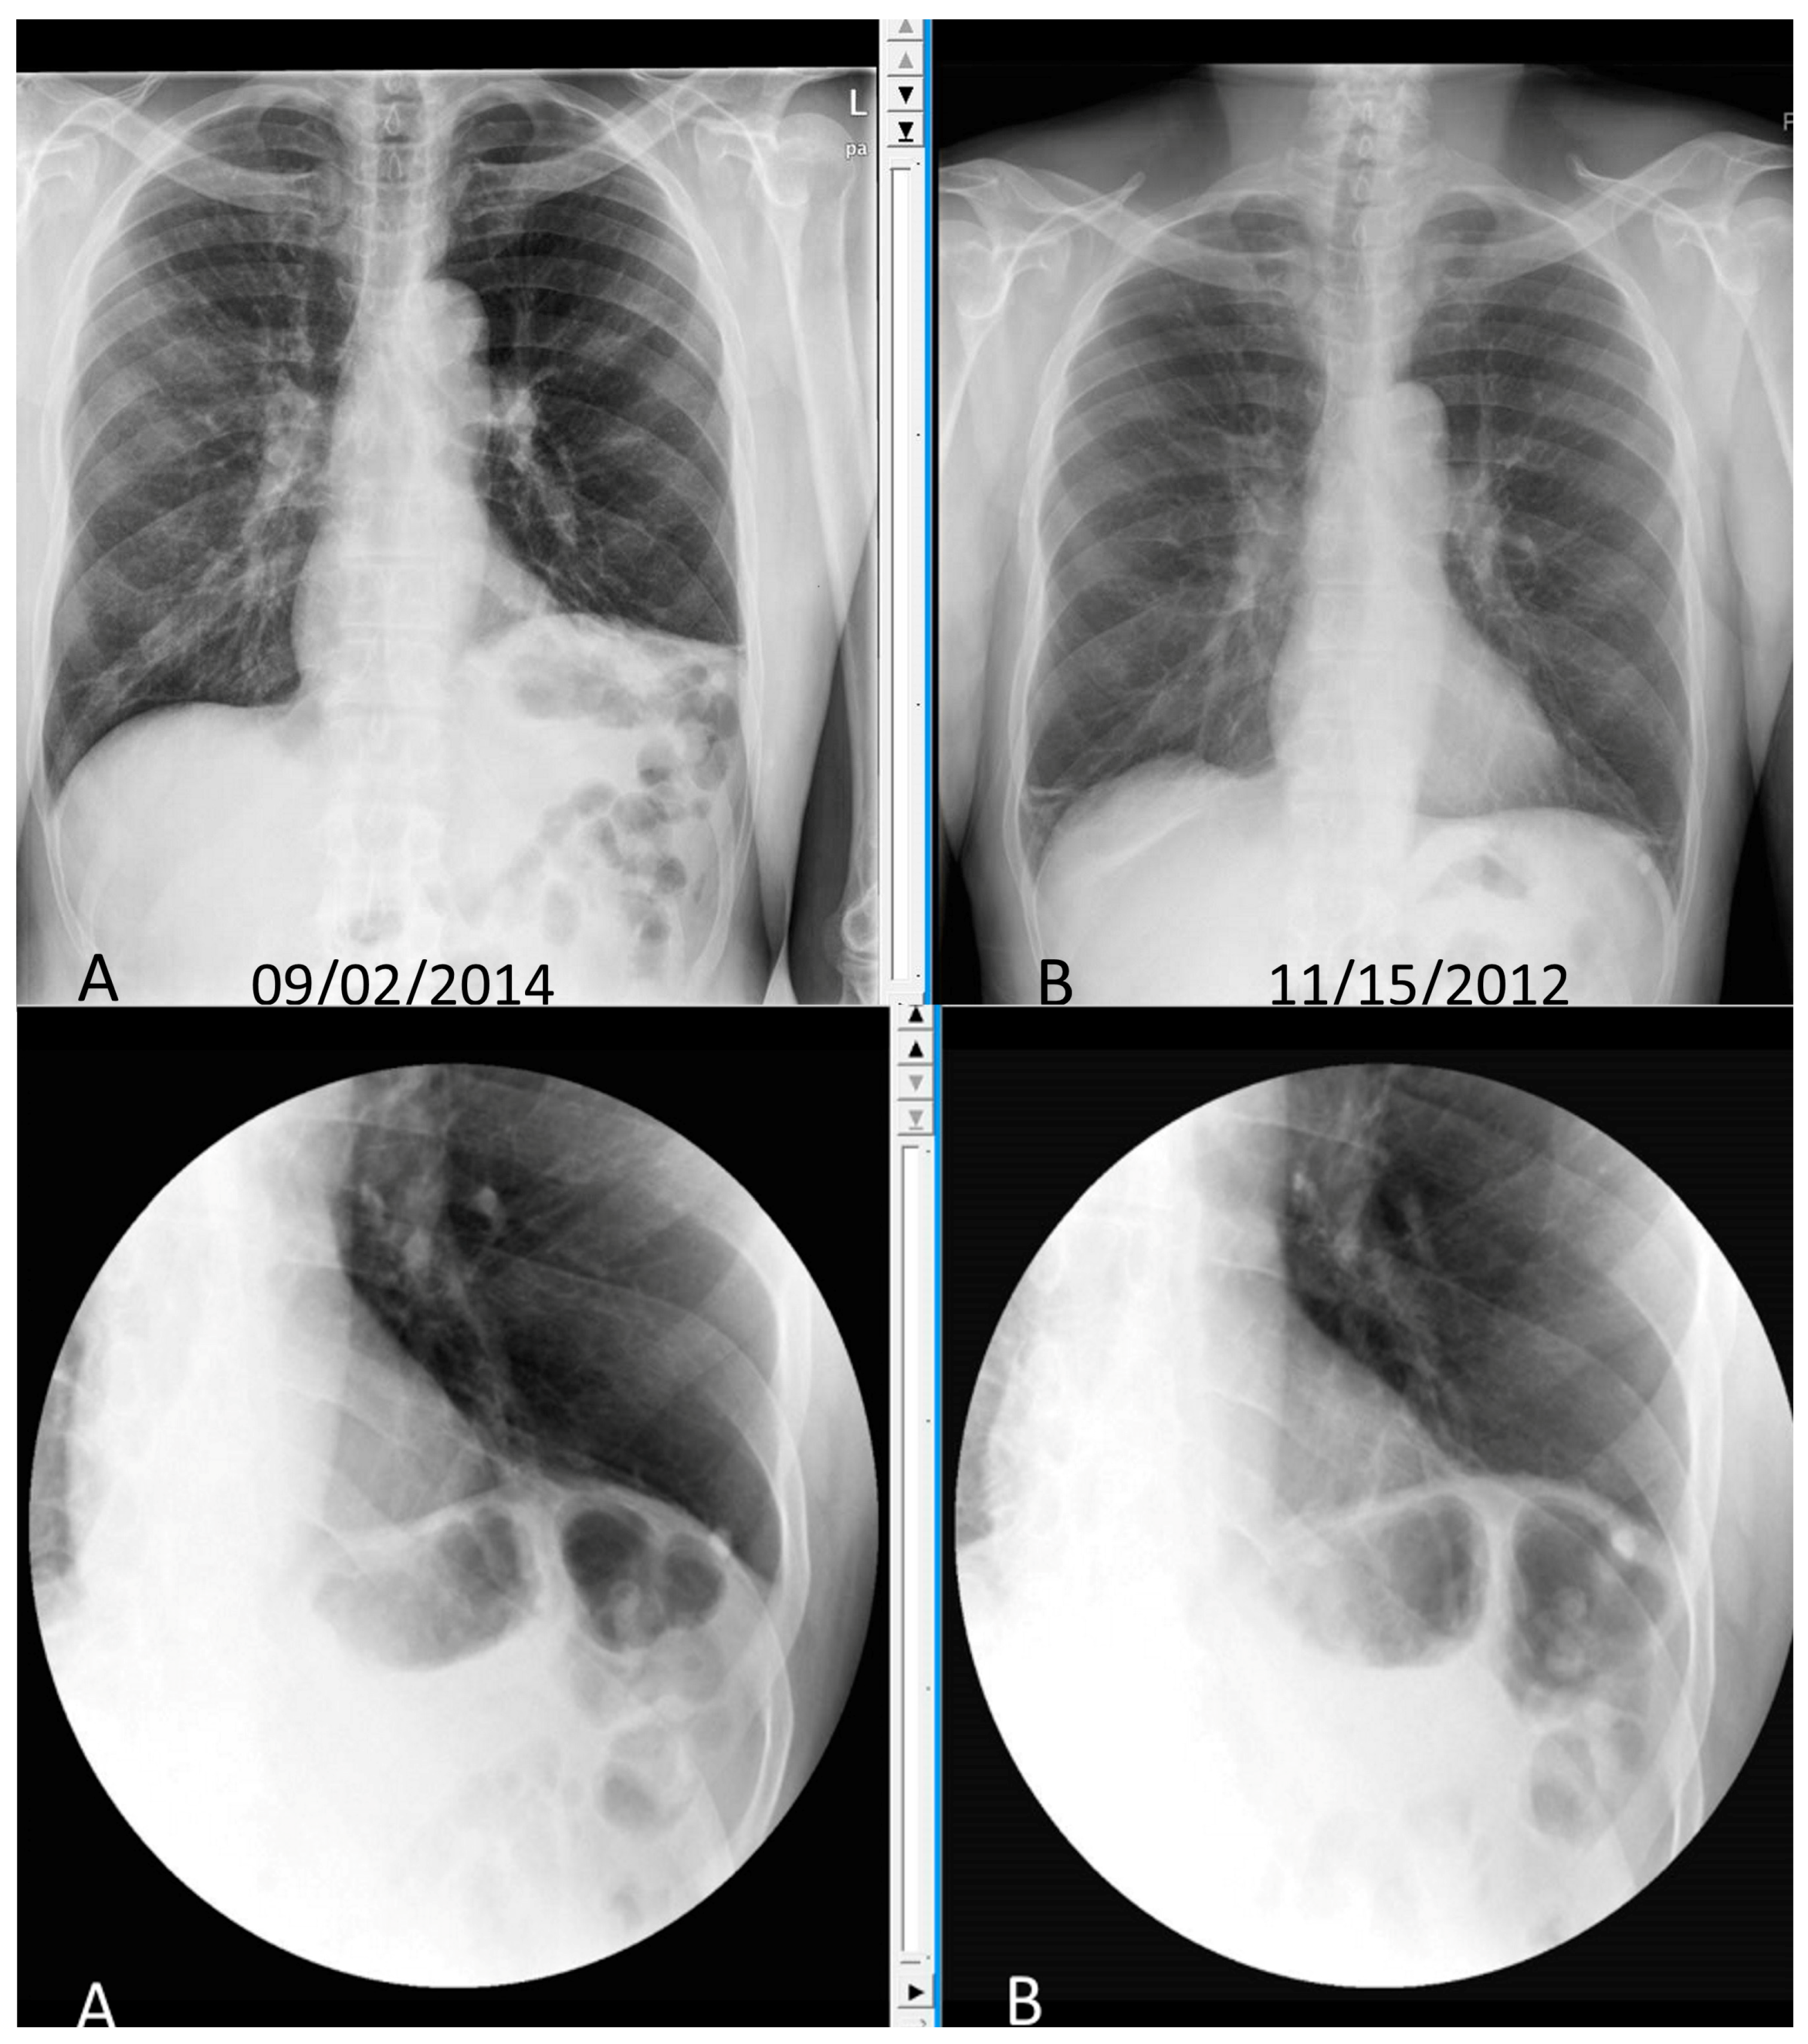

Pneumoperitoneum and subphrenic abscess are two important differential diagnosis of this radiographic sign which can be excluded out when normal plicae circulares or haustral markings of the colon is seen under the right diaphragm. If youre experiencing mild discomfort in your diaphragm take a few minutes to concentrate on deep breathing. Treatment depends on the type of hiatal hernia you have and on your symptoms.

Place one hand on your abdomen and breathe deeply. Reduced number of alveoli air sacs required for normal breathing. In severe cases when there is no simple treatment that can relieve dyspnea your doctor may prescribe morphine. Congenital diaphragmatic hernia CDH. There is usually a long history of heavy smoking. Shortness of breath may be accompanied by wheezing. Diaphragmatic dysfunction caused by transverse myelitis or leukemic infiltration of the cervical spinal cord in a patient with leukemia and shortness of breath. To treat phrenic nerve irritation This condition can be managed with a breathing pacemaker which takes over the responsibility of sending messages to the diaphragm. The cause for shortness of breath was thought primarily due to stable angina on tread mill test positive finding but Chilaiditis syndrome should also be considered as a cause for the shortness of breath.